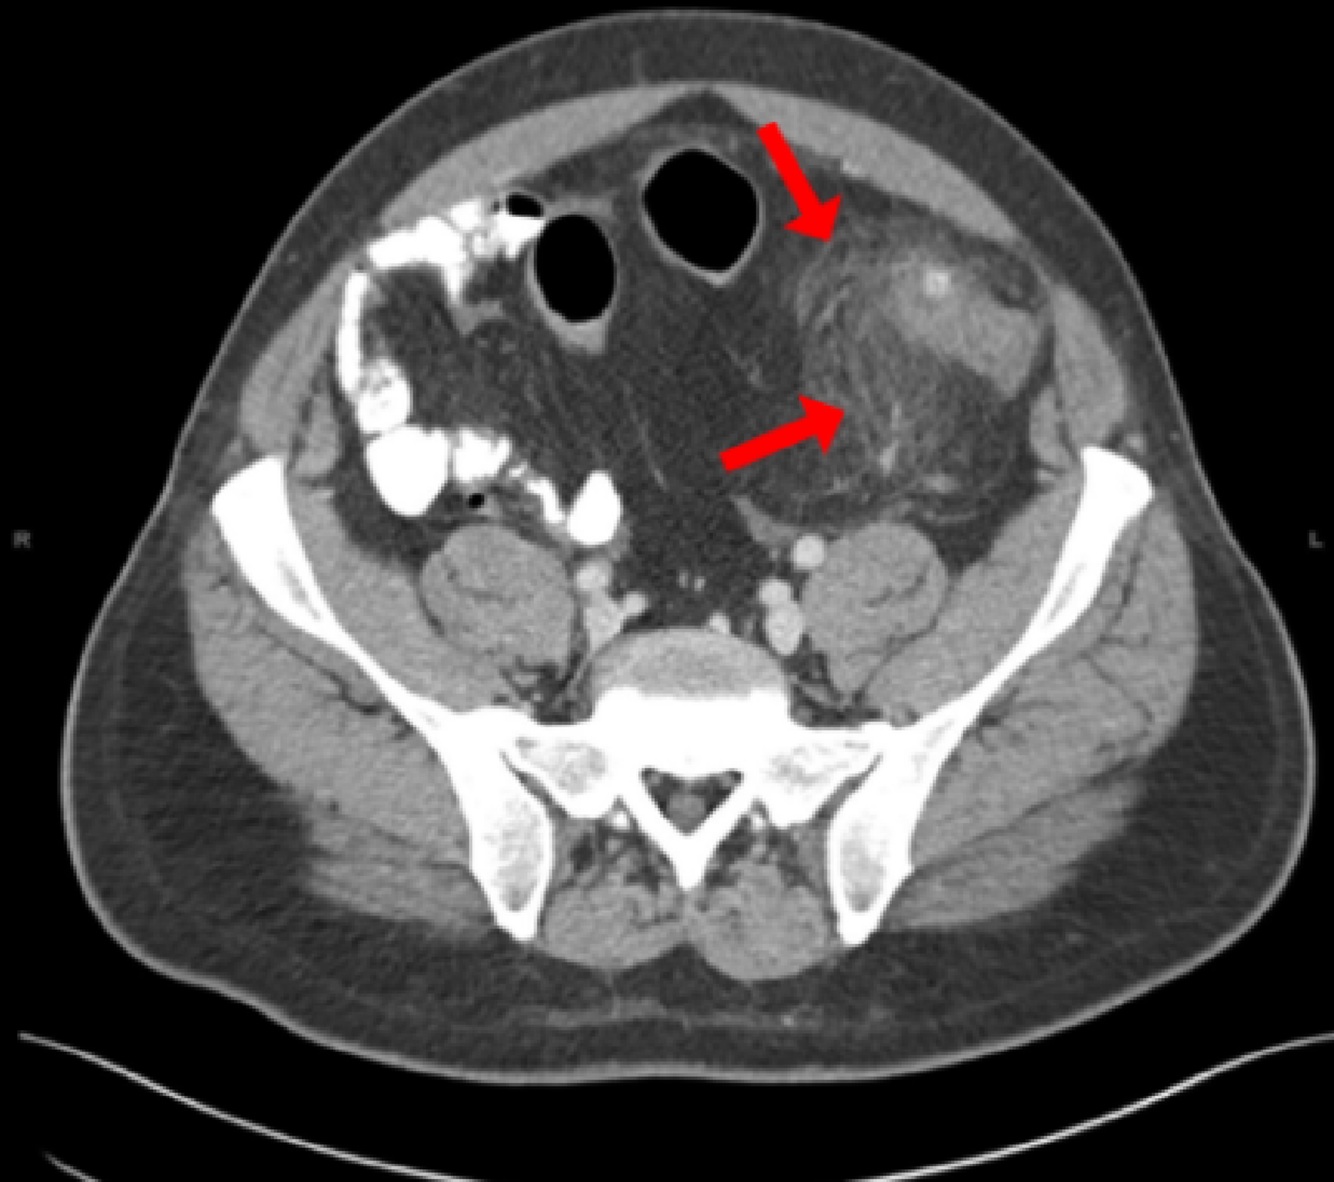

The biopsy results show well-differentiated hepatocellular carcinoma (HCC), also suggested by the hepatic nodule on imaging.